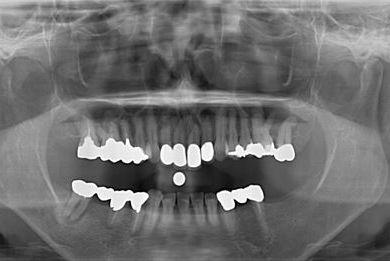

インプラントの症例写真 IMPLANT

インプラント治療+セラミック治療

| 治療内容 | インプラント2本、オールセラミック4本(ジルコニアフレーム、オールセラミック用の土台1本) | ||||||||||||||||||||||||||||||||

| 総治療費 | 1,299,000円 | ||||||||||||||||||||||||||||||||

| 治療期間 | 7ヶ月 |